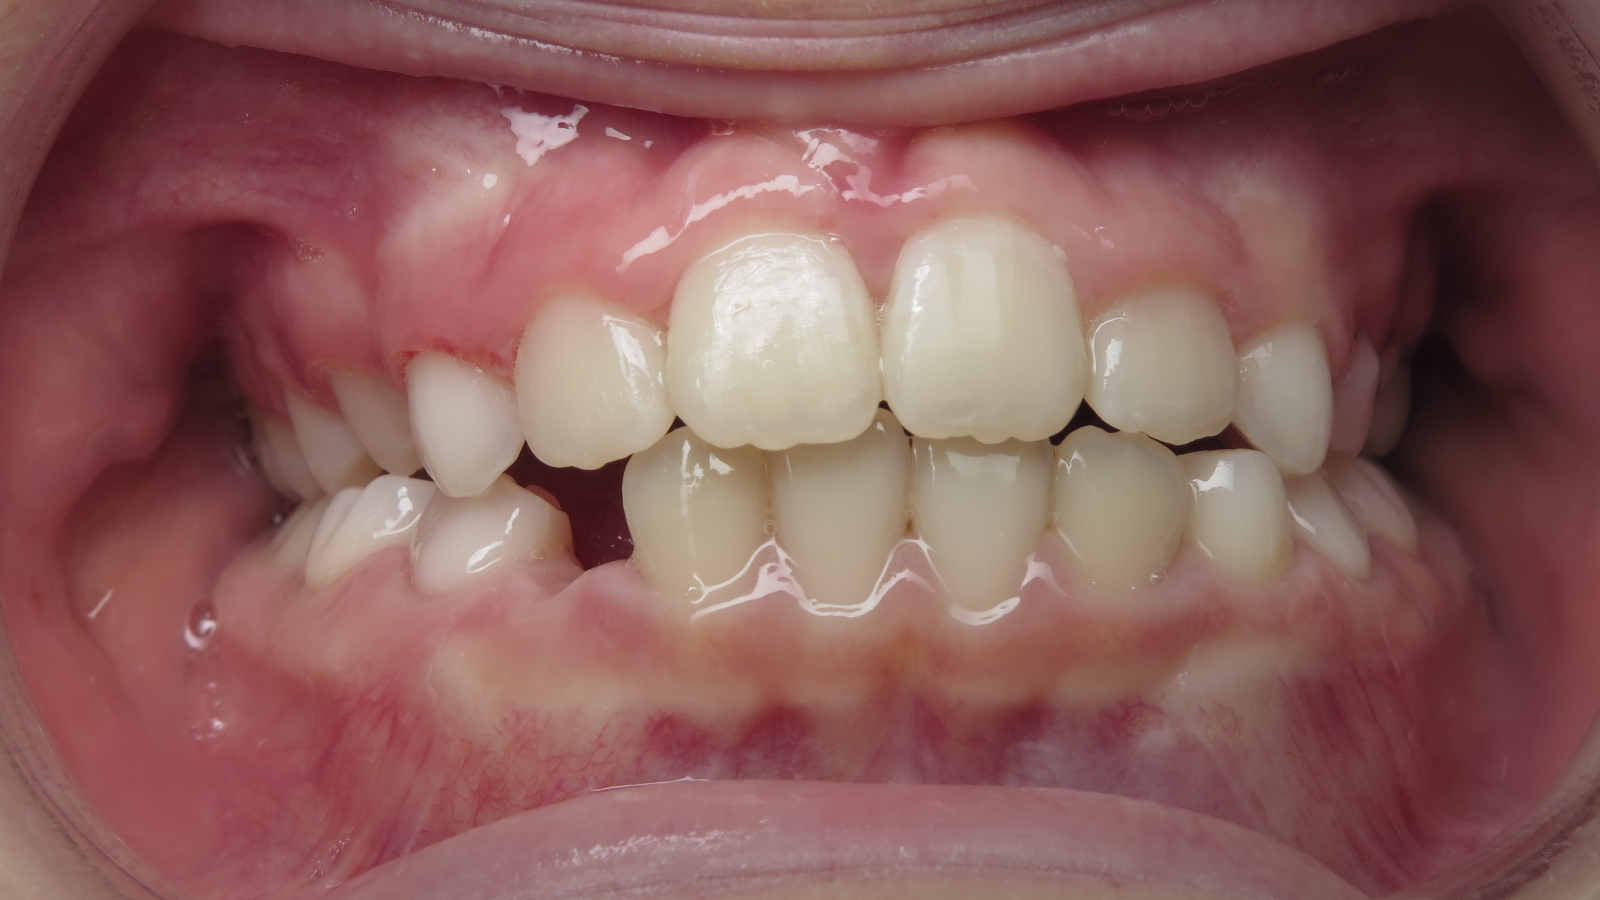

appareillage sectionnel multibagues pendant 18 mois

bilan début et en cours de traitement